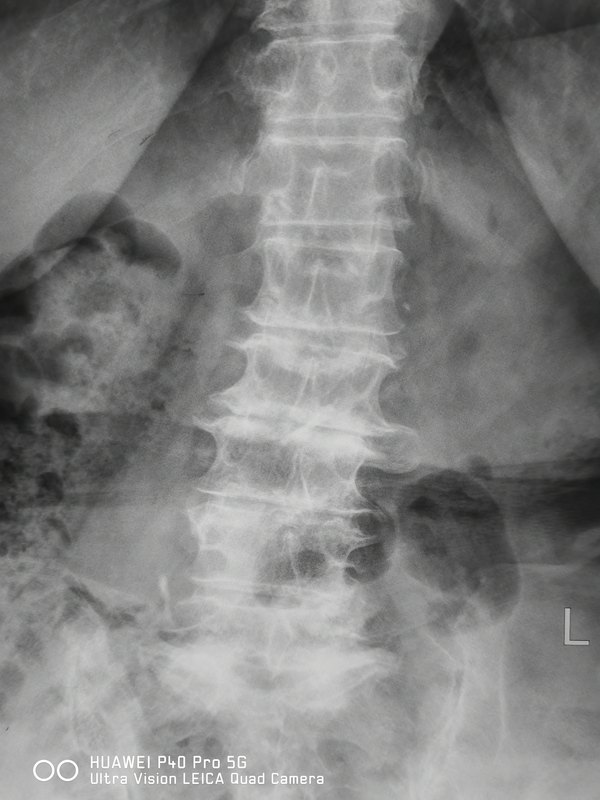

文/種濤 一位朋友家人,腰腿痛多年,近來加重,行走腰椎側(cè)彎達(dá)30多度才能勉強(qiáng)行走,臥床時(shí)下肢疼痛劇烈,徹夜難眠,查體腰部壓痛劇烈,放射至足,肌力感覺均有部分減退。影像學(xué)顯示腰椎多節(jié)段失穩(wěn)側(cè)彎,骨性椎管狹窄。有明確手術(shù)指征,且手術(shù)難度很大。 患者與家人堅(jiān)持保守治療,幾天后,癥狀緩解,3周后,自訴癥狀好轉(zhuǎn)六成,行走時(shí)腰椎能基本直立,睡眠行走等日常生活已無大礙。 感謝患者對醫(yī)院的信任,才能通過醫(yī)護(hù)聯(lián)合,醫(yī)患配合,以最小的代價(jià)減輕痛苦,重返家園。